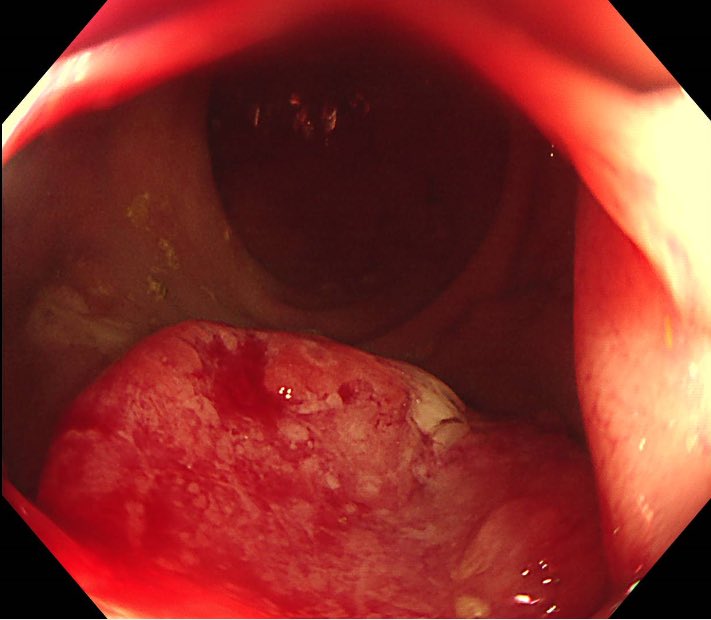

78 year-old woman. This lesion is located in the bulbar duodenum -anterior wall. What is optical diagnosis? Would you remove it?

This past week’s GI Grand Rounds was @UTSWMedCenter Third Space Endoscopist & @Parkland Director of Endoscopy, @TomTielleman, giving a talk on everything you’d want to know about big polyps! Optical diagnosis, when to refer, when/where to tattoo/biopsy, & resection techniques!